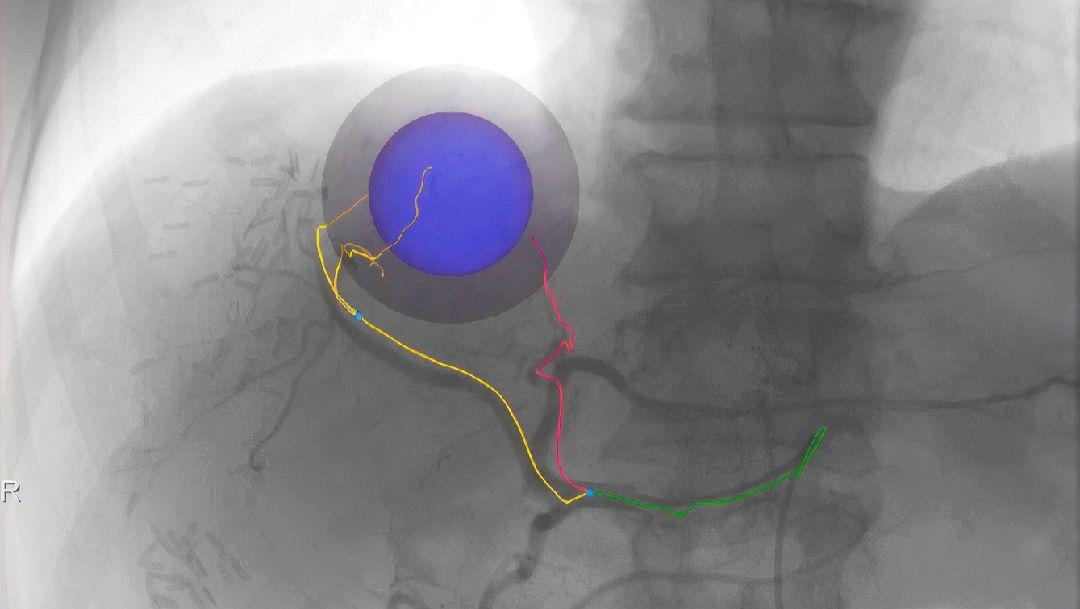

Predefined color coding facilitates finding the optimal treatment position for each tumor nodule.

Embolization combines the effects of regional chemotherapy with those of ischemic necrosis induced by arterial embolization. It takes advantage of the fact that the perfusion of hepatocellular carcinomas (HCC) and liver metastases from other types of cancer is mostly through hepatic arteries, allowing interventional radiologists to selectively deliver anti-tumor substances through the arteries.